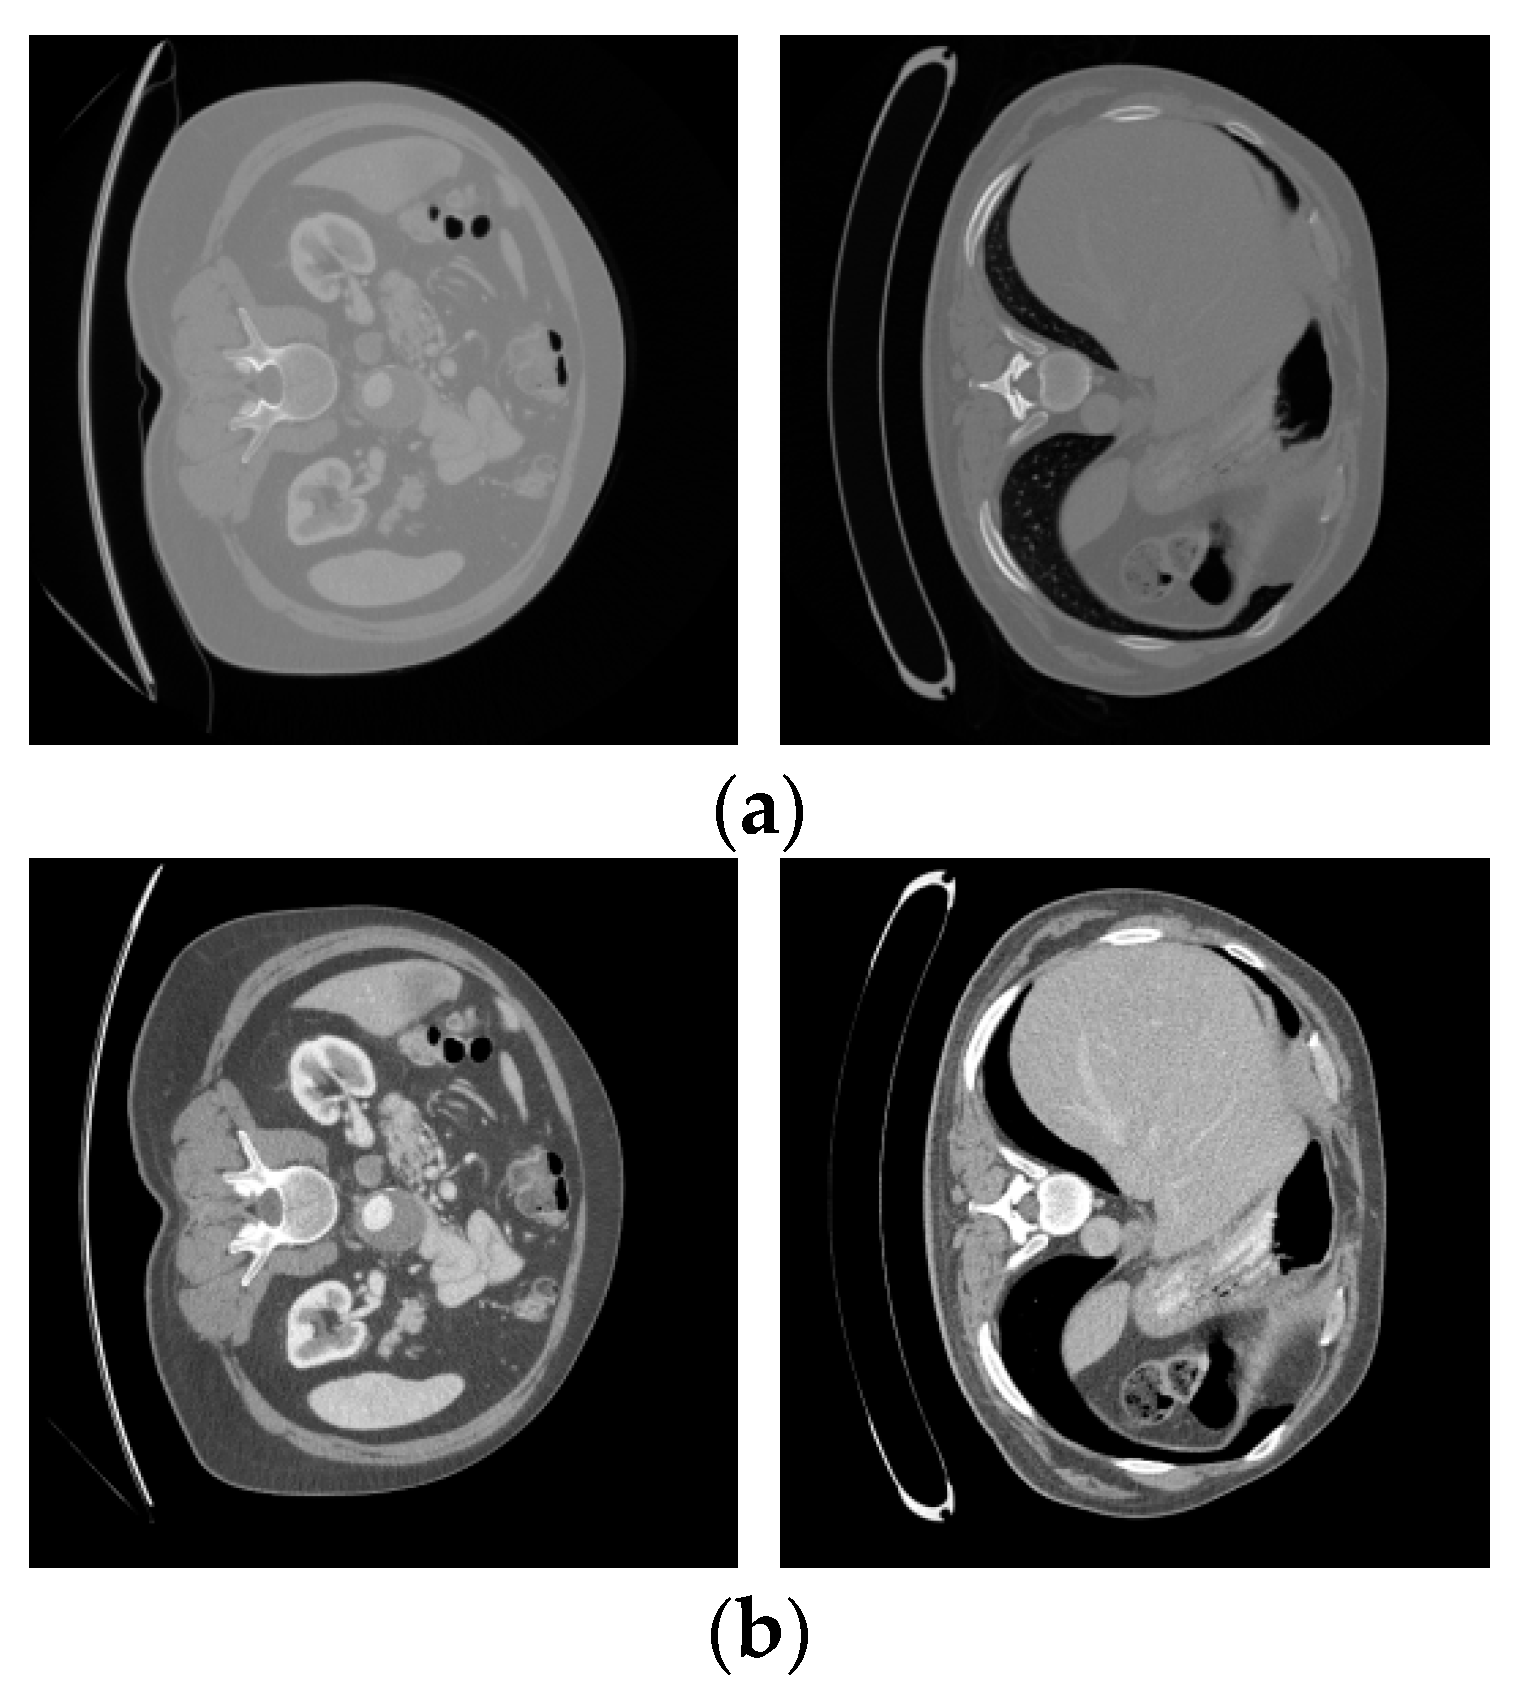

5.1. Dataset

5.2. Data Preprocessing